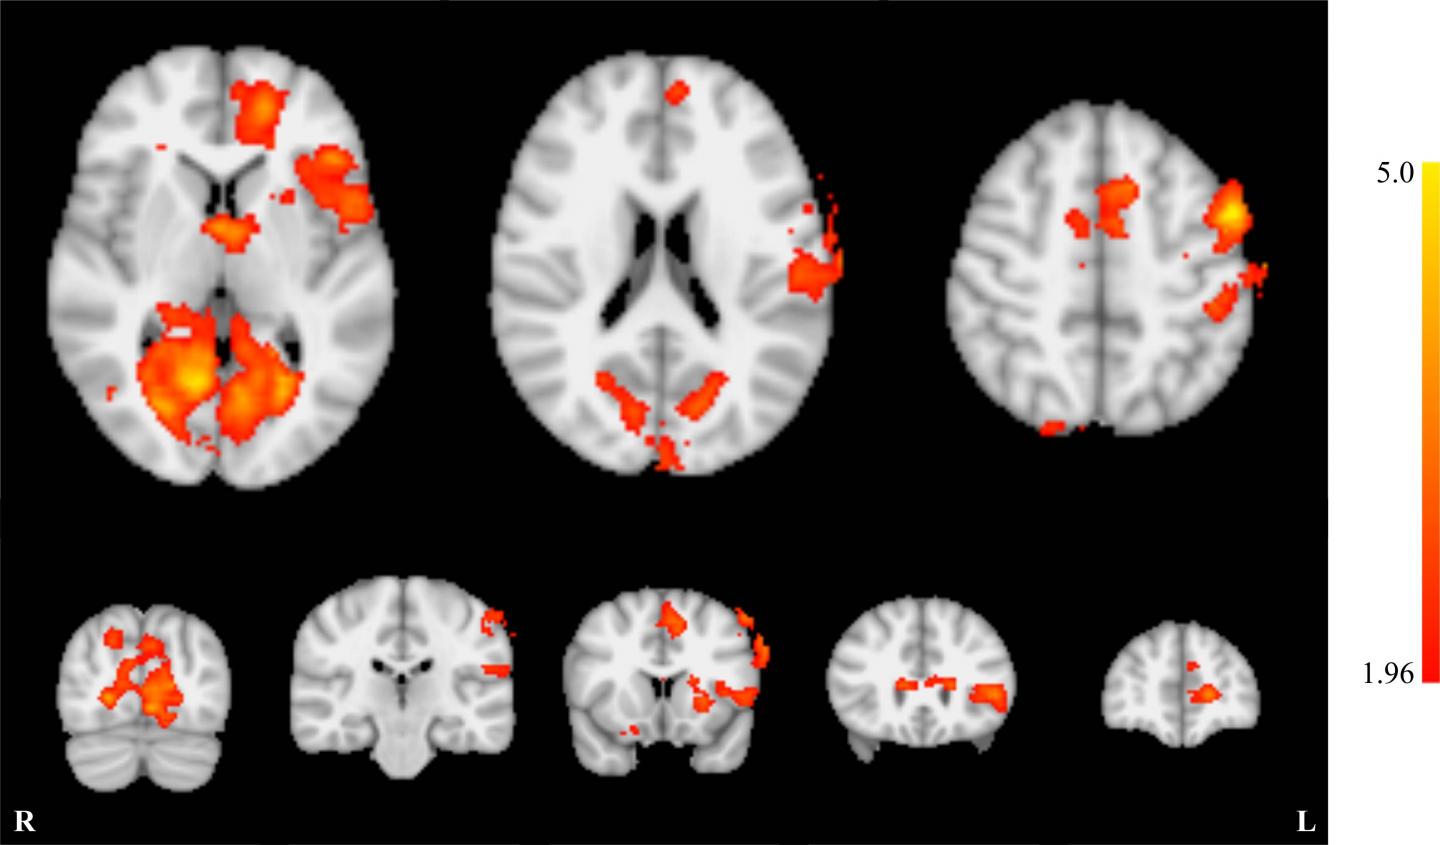

To obtain fMRI results, the researchers used single-shot echoplanar imaging, an MRI technique that is sensitive to blood oxygen levels, providing an indirect measure of brain activity.

"We started with alternating periods of sound and no sound in order to create a map of the brain and find areas that produced the highest activity during the sound phase," Dr. Sherwood said. "Then we selected the voxels that were heavily activated when sound was being played."

The participants then participated in the fMRI-neurofeedback training phase while inside the MRI scanner. They received white noise through their earplugs and were able to view the activity in their primary auditory cortex as a bar on a screen. Each fMRI-neurofeedback training run contained eight blocks separated into a 30-second "relax" period followed by a 30-second "lower" period. Participants were instructed to watch the bar during the relax period and actively attempt to lower it by decreasing primary auditory cortex activity during the lower phase.